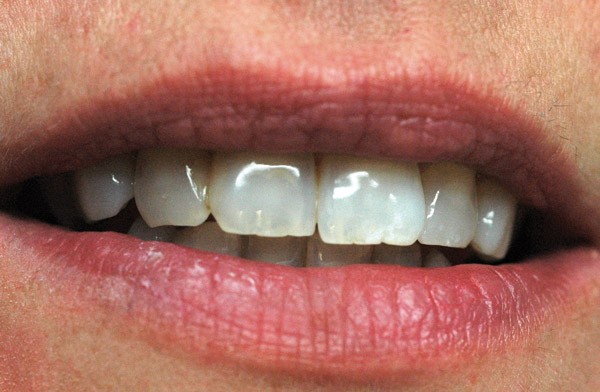

Nos yeux détectent plus les nuances de luminosité que les autres dimensions, elle est donc primordiale dans la définition d’une couleur. La couleur d’une dent se dessine par la superposition de tissus histologiquement et optiquement très différents allant de la pulpe à l’émail. Ces composants évolueront tout au long de la vie dans leur composition et épaisseur.

La saturation et la teinte d’une dent sont apportées par la dentine, mais dépendent de la translucidité et de l’épaisseur de l’émail.

Au fur et à mesure de la vie, l’épaisseur de l’émail diminue, il s’encrasse de chromophores. La dentinogenèse secondaire laisse apparaître une dent plus chromatique. À la suite d’une agression, la dentine réactionnelle génère un tissu plus saturé.

La couleur d’une couronne varie ainsi du bord libre à la zone cervicale, en fonction de la quantité des différents tissus qui la composent. Plus translucide au niveau du bord libre en raison d’une proportion d’émail très importante, la dent est plus opaque au niveau de la zone cervicale, laissant davantage apparaître la dentine.